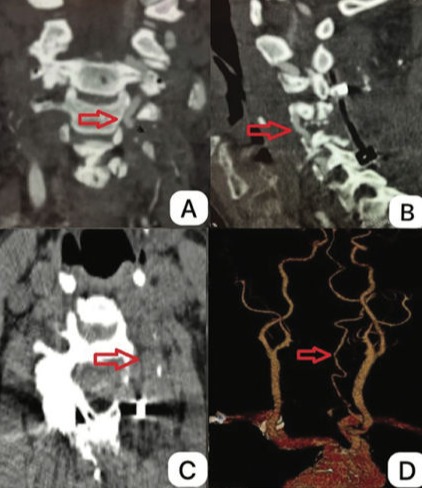

A síndrome de Bow Hunter se manifesta quando a artéria vertebral é comprimida após a rotação da cabeça. A compressão sintomática com estenose da artéria vertebral devido a osteófitos cervicais é uma causa rara e ocorre devido a um processo degenerativo progressivo. Geralmente, a compressão se origina anteromedialmente do processo uncinado e é assintomática devido à competência da artéria vertebral contralateral.

No paciente descrito, a compressão se apresentou superomedialmente devido a osteófitos na faceta articular superior da vértebra C5, e a artéria vertebral contralateral estava obstruída. Uma avaliação cuidadosa com imagens, principalmente angiotomografia 3D pré-operatória, é necessária para determinar a abordagem mais benéfica para a descompressão. O tratamento de escolha para compressão sintomática induzida por espondilose cervical é a cirurgia de descompressão.